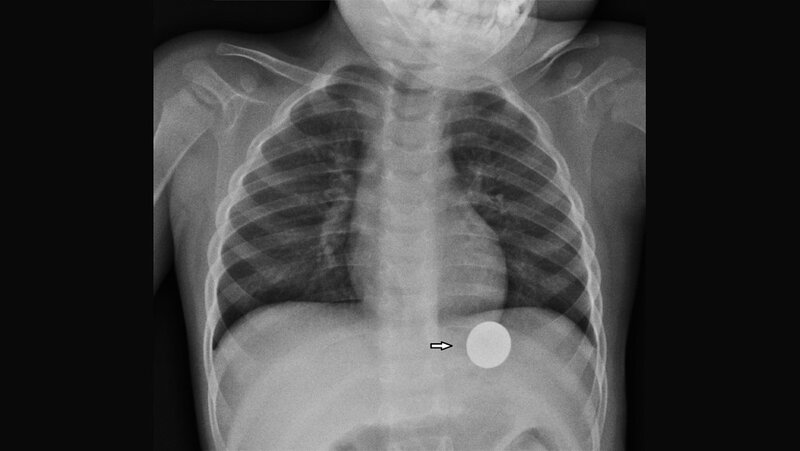

Artefakte können die diagnostische Qualität der Aufnahmen beeinflussen. Auch in der Radiotherapie müssen für eine exakte Therapieplanung die Artefakte reduziert werden. Metallische Implantate können in der Magnetresonanz-Bildgebung erhebliche Artefakte verursachen, insbesondere Signalverluste, Signalverstärkungen, geometrische Verzerrungen und Veränderungen in der Fettsuppression. Die Zusammensetzung des Prothesenmaterials bestimmt das Ausmaß der Artefakte und die Qualität der MR-Aufnahmen.

Artifacts may influence the diagnostic quality of the images. In radiotherapy treatment planning, the reduction of CT artifacts is also very important. Metal implants cause severe artifacts on MRI, especially in signal-loss, signal-pileup, geometric distortion, and failure of fat-suppression. The composition of prosthetic implants is decisive in determing the quality of MR imaging.